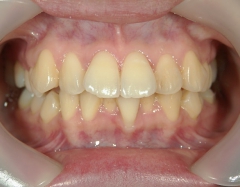

矯正歯科 治療前